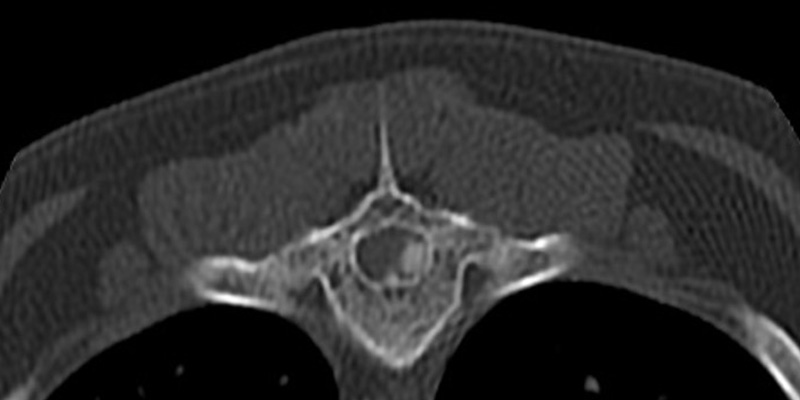

Max was examined; it was noted that he was experiencing Grade II (of V) paraparesis – he was ambulatory but with decreased proprioception (awareness of positioning and movement of the limbs). A computerised tomography (CT) scan showed approximately 40% compression of the spinal cord at thoracic vertebra 11 and 12 due to spinal disc extrusion.

Max’s T11 vertebra (axial view) showing disc material compressing the spinal cord: cause of paresis